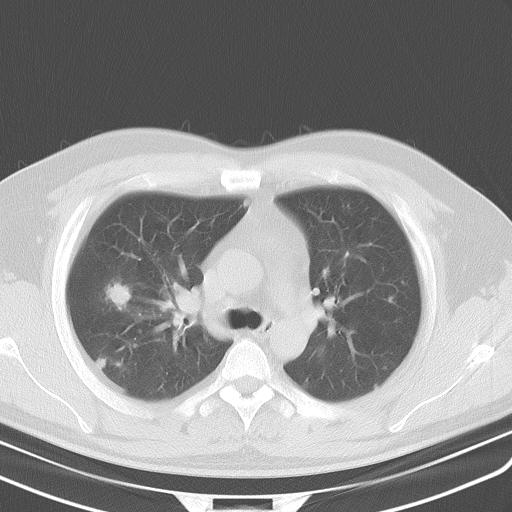

标题: CT13304:胸部多发结节影,少见,请会诊!!!! [打印本页]

标题: CT13304:胸部多发结节影,少见,请会诊!!!!

患者男性 35 主因发热咳嗽四天,血象不高,心肺听诊未见异常,无其它病史及传染病接触史。

双肺散在多发类圆形结节灶,边缘较光滑,纵隔淋巴结肿大,考虑转移瘤

淋巴结近呈对称性肿大,肺部多发结节,首先考虑结节病,其次考虑转移瘤。

肺内多发大小不等结节影,以外周为著,纵隔见多个淋巴结肿大;结果病人,35岁,有发烧咳嗽等病史,首先考虑血源性肺脓肿可能性大,建议积极抗炎治疗后复查,除外转移瘤或韦格氏肉芽肿.

双肺及胸膜下见多发结节影,最大直径约0.4,内密度均匀,中纵隔腔静脉后见小淋巴结影。

首先考虑转移瘤,建议查原发灶;